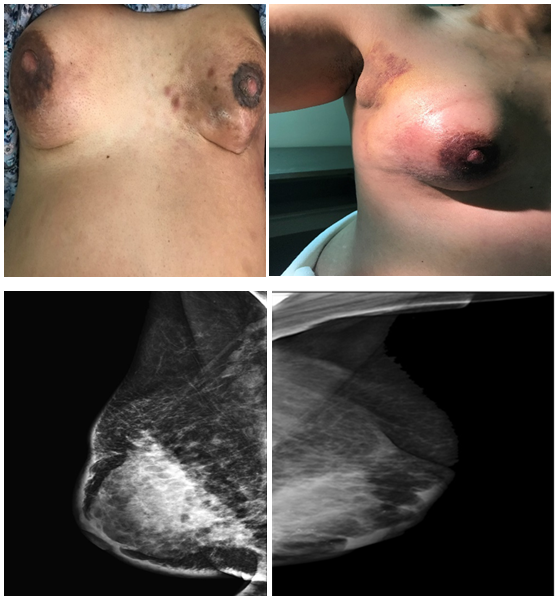

Case Report and Literature Review: Unusual Presentation of Genitourinary & Gastrointestinal Metastases from Invasive Lobular Carcinoma of the Breast

Khadija Al-Musalhi, Badryia Al-Qassabi, Radiya Al-Ajmi, Suad Al-Aghbari

International Journal of Innovative Research in Medical Science·July 4, 2020